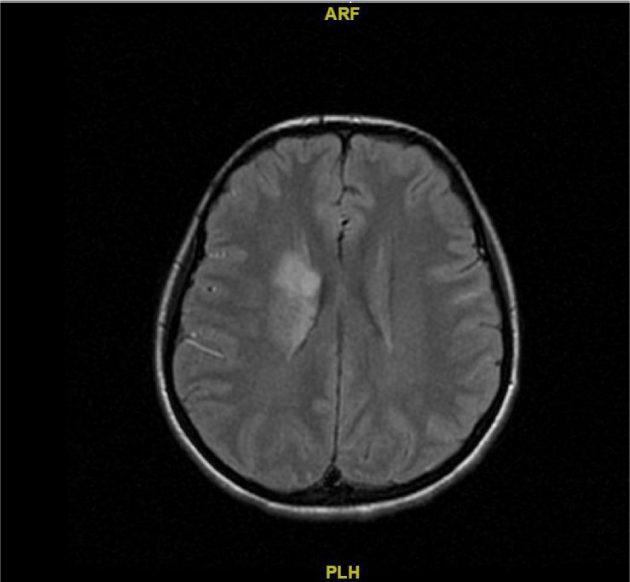

23 years old female patient with acute thematic fever history in her childhood was referred to our neurology clinic with complaints of numbness and loss of strength in left arm and left leg which were observed 2 weeks after tooth extraction. Her fever was 38,2°C there was the loss of strength in left arm and left leg with a newly developing heart murmur. Complete blood count showed that leukocyte count was 24500 103µL. Consequently, the patient was admitted to neurology clinic and forwarded to diffusion MRI. The diffusion MRI showed a newly developing stroke in the right parietal region (Figure 1). A cardiology consultation has been requested due to cardiac bruit and fever. Transthoracic echocardiography revealed rheumatic mitral valve disease causing mild mitral stenosis and vegetation's with 18x10 mm size on the atrial surface of the mitral valve and 10x5 mm on the ventricular surface of the aortic valve (Figure 2). Consecutive two blood cultures drawn more than 12 hours apart were positive for streptococcus pneumonia; therefore the patient has been diagnosed with endocarditis with double valve involvement. Transthoracic echocardiography and blood cultures were taken together and the patient was diagnosed as infective endocarditis according to Dukes diagnostic criteria. The treatment was started with gentamicin and penicillin and continues for 6 weeks. No fever has been observed after the 2nd day of treatment. TTE performed at the 5th day of antimicrobial treatment showed that size of the vegetation on the mitral valve was reduced to 12x6 mm while the vegetation on the aortic valve was reduced to 7x4 mm.

Figure 1: